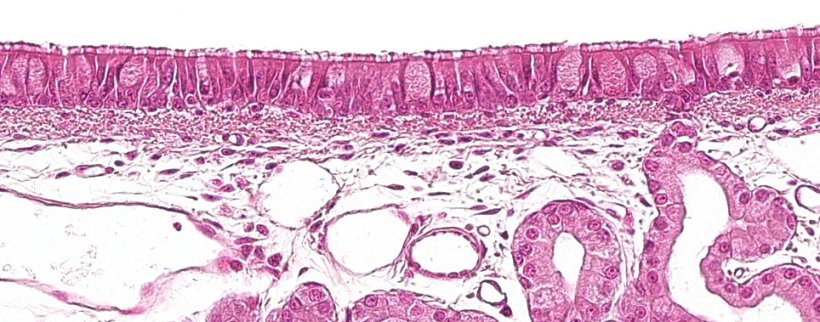

A primeira parte do sistema respiratório, a porção condutora ou vias aéreas, vai da cavidade nasal até às últimas ramificações dos bronquíolos, e também inclui os seios nasais e paranasais que estão conectados à cavidade nasal, nasofaringe e laringe. Todas estas estruturas tubulares estão revestidas por um epitélio pseudo-estratificado ciliado com células caliciformes (figura 1), responsável por um dos principais sistemas de defesa da mucosa respiratória, o aparelho mucociliar. Este sistema é composto pelos cílios das células do epitélio respiratório, junto com as secreções das células caliciformes e as glândulas seromucosas que aparecem sob a mucosa respiratória e a sua principal função é eliminar as partículas que entram através do ar inspirado. As glândulas segregam um líquido claro, de baixa viscosidade e rico em proteínas, que se dispõe entre os cílios, formando um meio que favorece seu movimento para cima. O muco segregado pelas células caliciformes é depositado nos cílios e permite a aderência das partículas inaladas. O movimento ascendente dos cílios empurra o muco em direcção à parte superior do sistema respiratório, que pode ser engolido e passado para o sistema digestivo, onde é digerido, ou expelido para fora pela boca e / ou cavidade nasal. Agentes como Mycoplasma hyopneumoniae, que provoca a perda dos cílios, ou vírus como o da gripe suína ou o coronavírus respiratório, que provocam a destruição das células epiteliais, levam a cabo a sua acção patogénica destruindo este sistema defensivo.

Figura 1: Epitélio pseudo-estratificado ciliado com células caliciformes característico do aparelho respiratório